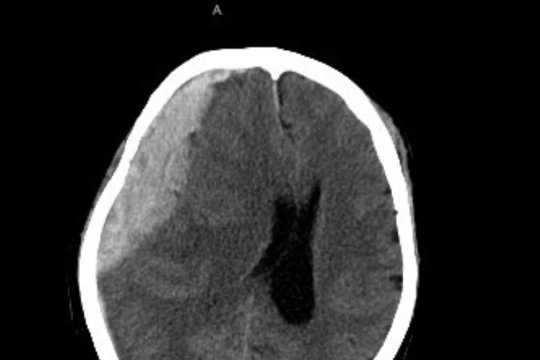

Ngã đập đầu xuống đất, cụ bà vỡ mạch máu não, liệt nửa người VietTimes – Không may bị ngã đập đầu xuống đất, cụ bà 84 tuổi vào viện trong tình trạng liệt nửa người.